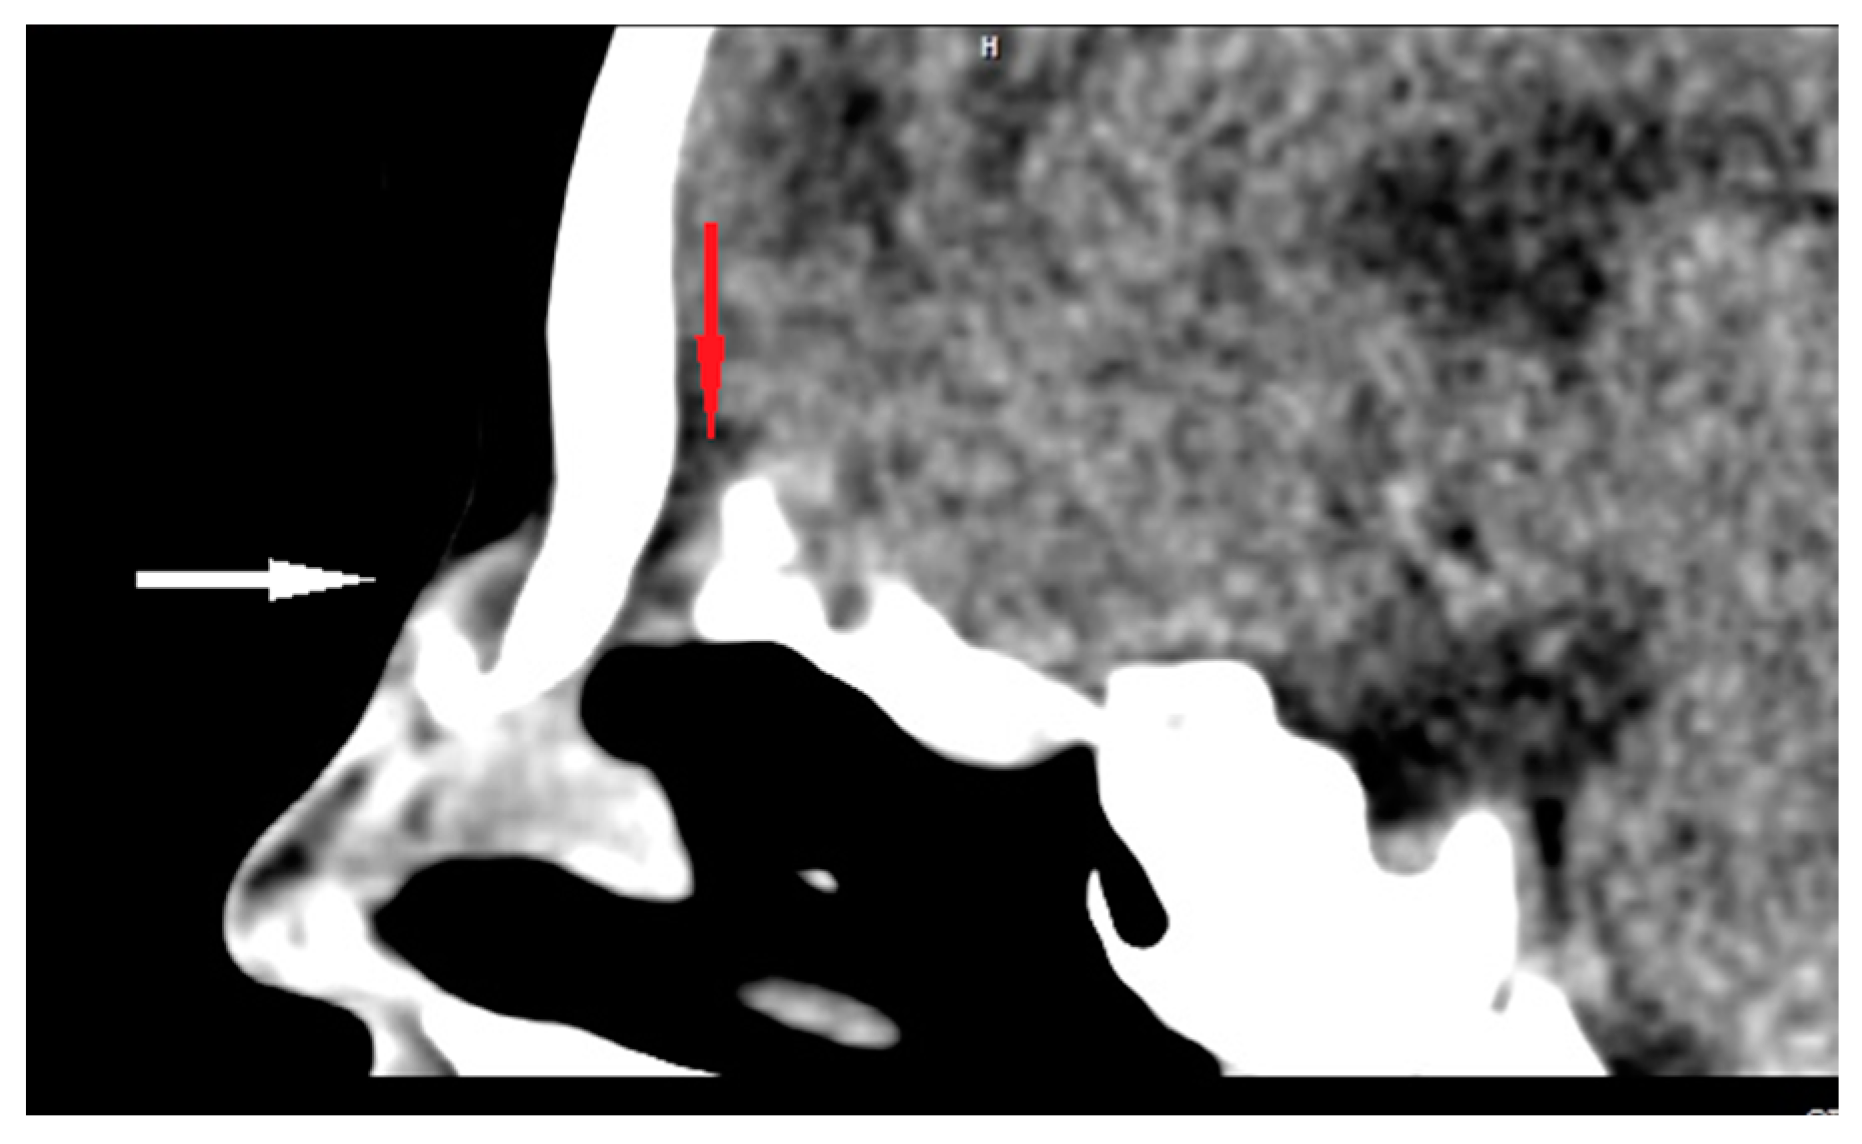

| Radiological characteristics | CT | No correlation between the particular location of the sinus ostium or cyst and the presence of intracranial extension; bifid crista galli and widening of foramen caecum (suggestive of intracranial extension); dermoid cyst—density of fat; epidermoid cyst—density of water | Bony defect may be revelaed | Developmental bony defect of the skull base |